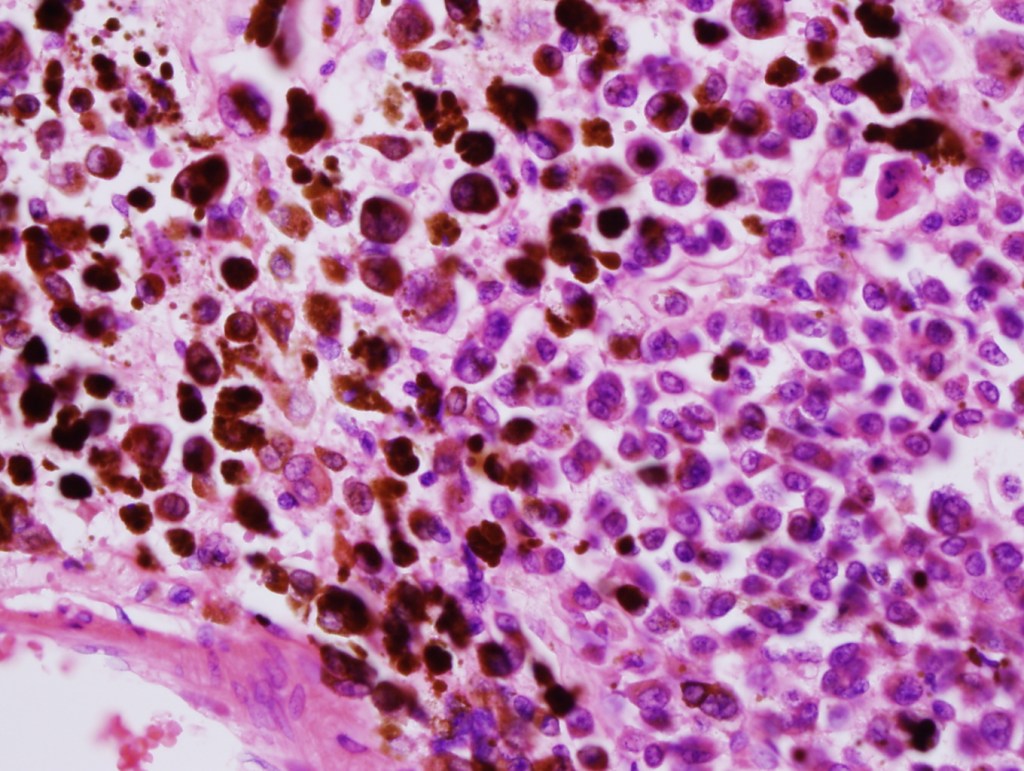

Melanoma arising in a congenital nevus

•Although the vast majority arise in giant forms, they may be encountered in smaller lesions & can be present at birth

•Develop in the dermal component

•Typical melanoma, nevoid melanoma, small cell melanoma, pleomorphic/anaplastic melanoma, melanoma with heterologous differentiation & malignant nerve sheath-like melanoma.

This melanoma arose in a small congenital nevus of the scalp. It metastasized widely. Varying features in different fields.